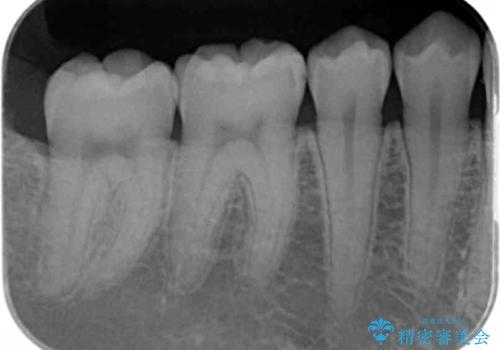

矯正後の虫歯治療 セラミックインレーでの治療

- 矯正後の虫歯治療です。

咬む面と歯と歯の間の虫歯に対してセラミックインレーでの修復処置をしていきます。

- 右下6 セラミックインレー 77,000円費用は治療当時の料金となります